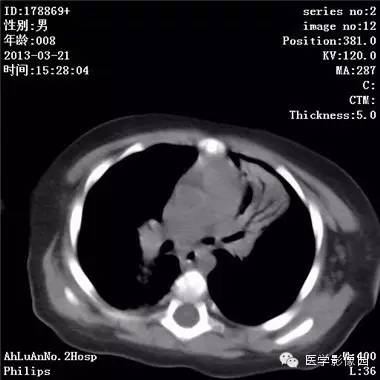

患儿男,8个月,呛咳,发热一周。实验室检查白细胞及中性粒细胞增高。

两肺肺纹理增多、增粗,右肺可见斑片状、片絮状模糊影,边界欠清;左肺上叶见楔形高密度影,内可见支气管征,尖端指向肺门;左肺下叶肺野透亮度增强;另见左肺主支气管内可见块状软组织密度影。

支气管异物(花生米)伴两肺炎症(追问病史,患儿奶奶层于一周前喂食患儿花生米,当时疑似“呛进去”,后来见好了也就没留意)。